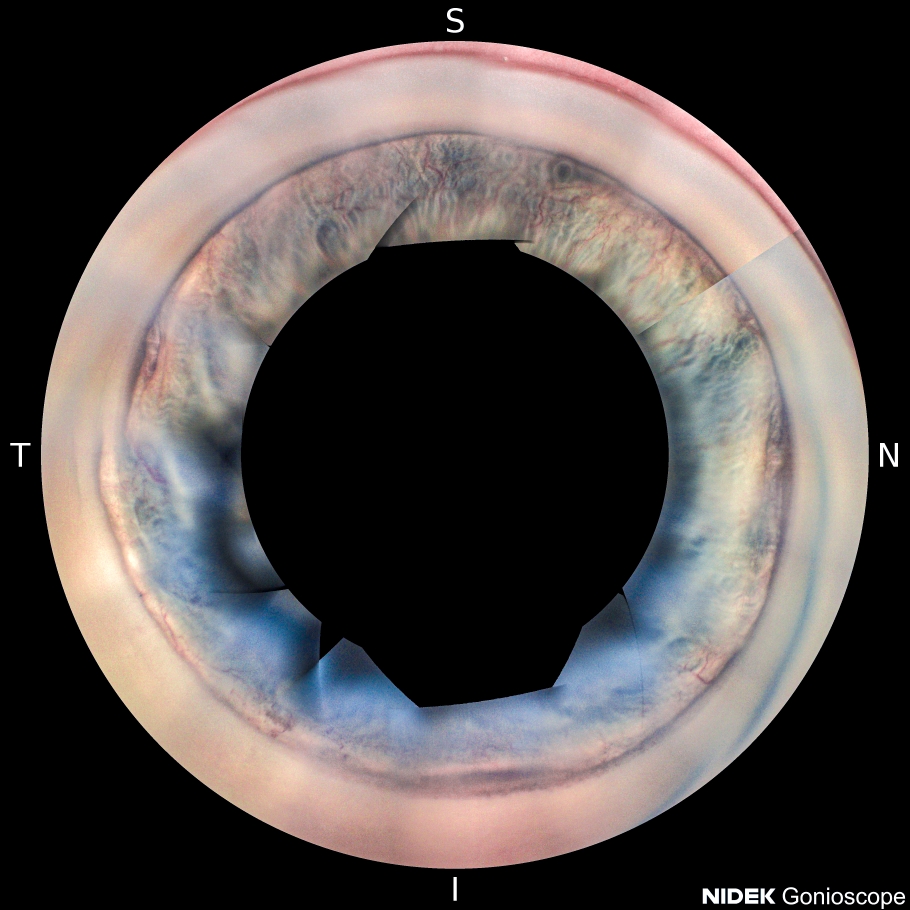

Комбинированное лечение неоваскулярной глаукомы на фоне тромбоза центральной вены сетчатки (клинический случай)

Цель. Представить особенности клиники и оценить эффективность лазерного и хирургического лечения пациентов с неоваскулярной глаукомой на фоне перенесенного тромбоза центральной вены сетчатки.

Материал и методы. Обследованы два пациента с вторичной неоваскулярной глаукомой вследствие тромбоза центральной вены сетчатки. Выполнены оперативные вмешательства: пациенту М. - микроимпульсная циклофотокоагуляция (дважды), интравитреальное введение ингибитора ангиогенеза (5 инъекций), лазеркоагуляция сетчатки (двухэтапная); пациенту Е. - микроимпульсная циклофотокоагуляция, интравитреальное введение ингибитора ангиогенеза (2 инъекции), имплантация клапана Ahmed.

Результаты. В результате проведенного лечения была достигнута компенсация внутриглазного давления, улучшение зрительных функций, снижение неоваскуляризации структур переднего отрезка глазного яблока.

Обсуждение и заключение. Микроимпульсная циклофотокоагуляция может применяться в комплексном лечении неоваскулярной глаукомы на любом этапе с целью снижения ВГД и уменьшения неоваскуляризации радужки и структур угла передней камеры в послеоперационном периоде.